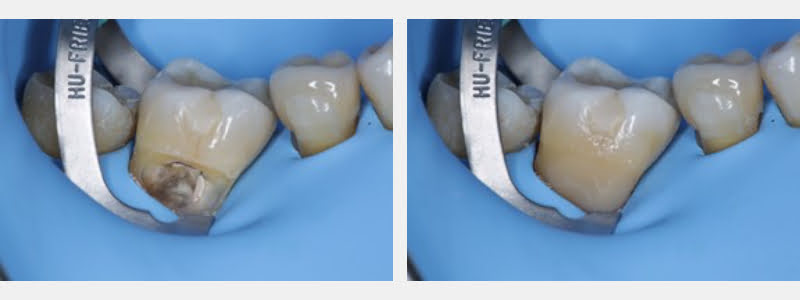

- Alternated placing the modified 212 clamp over the teeth to be restored to decrease the time the teeth had a clamp to help decrease the mechanical retraction caused on the gum tissue.

- Began treating the most distal tooth to decrease patient exhaustion during the procedure.

- Conditioned the substrates using hydroabrasion with 29 microns aluminum oxide at 2 psi on enamel and dentin.

- Selective etch of enamel for 30 seconds with phosphoric acid 37%.

- Rinsed and dried the cavities.

- Used a two-step adhesive system.

- Adhesive polymerization.

- Pre-heated composite resin stratification of the restoration.

- Performed finishing and polishing of the restoration using polishing discs.